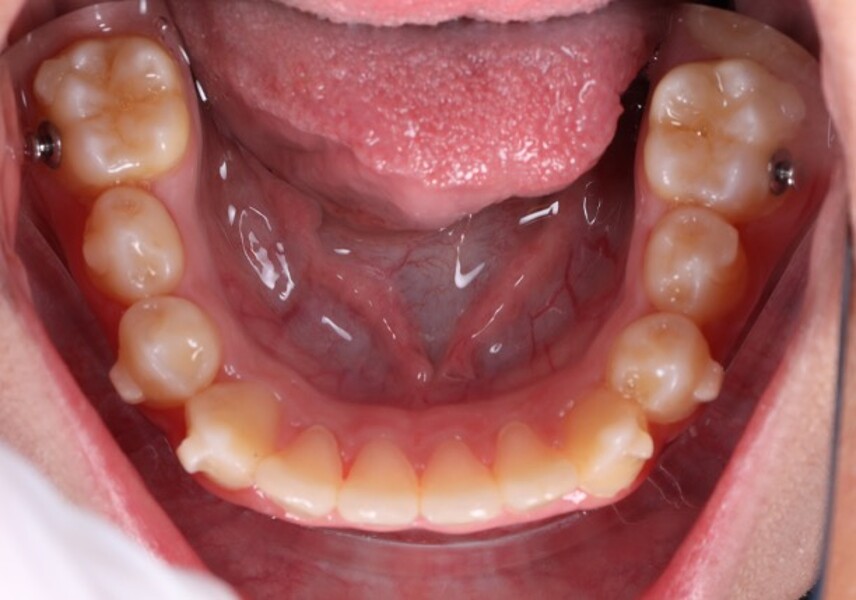

Figs. 6a–e: Intra-oral photographs after the first phase of treatment.

At the end of the first phase of treatment, the clinical findings included (Figs. 5 & 6):

Class I molar and canine relationships on the left side;

half-cusp Class II relationships on the right side;

normal overjet (2.0 mm) and overbite (2.5 mm); and

a posterior open bite, particularly on the left side.

Cephalometric analysis showed that the sagittal discrepancy had been significantly reduced (ANB = 3.7°; Wits = 1.8 mm). Mandibular length remained below normative values.